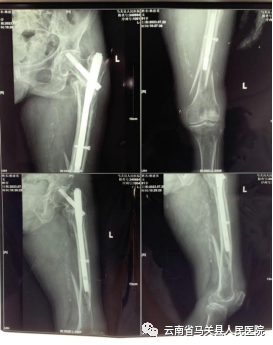

主管医生详细询问病史、认真体检,获悉侬奶奶1年前因左股骨转子间骨折,曾行“左股骨骨折髓内钉内固定术”,因侬奶奶身体一直欠佳,且年事已高,家人担心身体无法耐受手术治疗,故一直未进行内固定物取出,髓内钉一直留存体内。主管医生与家属做了详细沟通,认为目前手术是改善老人病情的最佳办法,如果不及时治疗,长期卧床容易发生褥疮、肺部感染、深静脉血栓等并发症,且断骨可能无法愈合。

术前检查照片